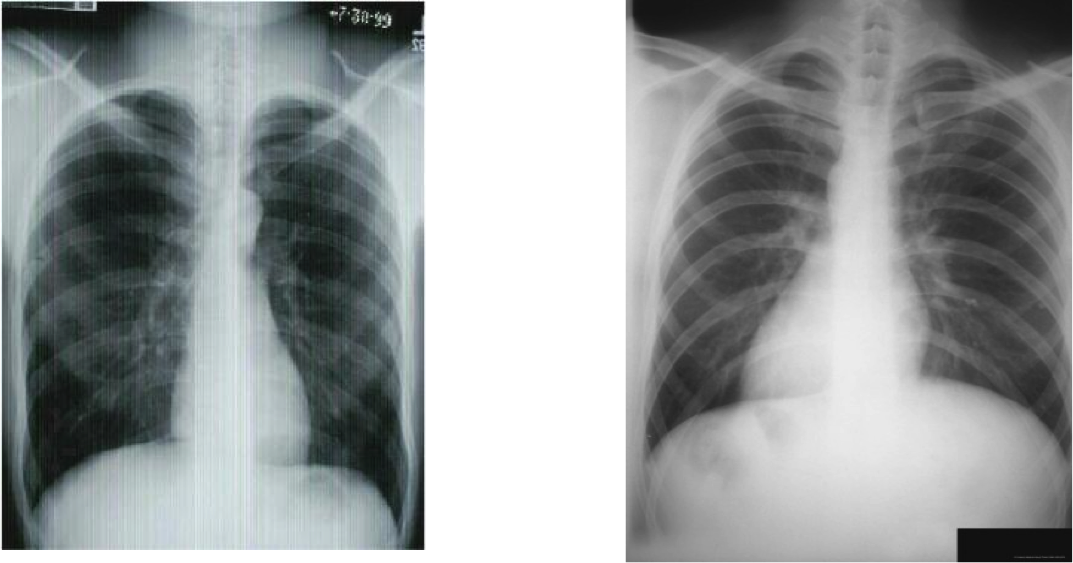

On the following CXR, which image is of a patient with Bronchitis?

Left - Bronchitis, note: darker is more air

Right - normal